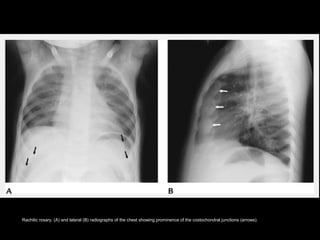

RicketsRickets

• The regions of highest yield on

radiologic evaluation of rickets are those

that are undergoing rapid growth.

– Costochondral junctions of middle ribs

(rachitic rosary)

– Distal femur

– Both ends of the tibia

– Distal radius and ulna

– Proximal humerus.

Rachitic rosary. (A) and lateral (B) radiographs of the chest showing prominence of the costochondral junctions (arrows).